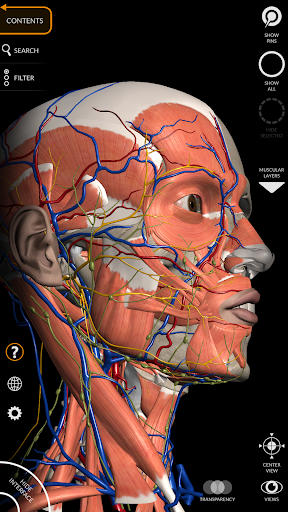

يتيح لك "Anatomy 3D Atlas" دراسة التشريح البشري بطريقة سهلة وتفاعلية.

من خلال واجهة بسيطة وبديهية، من الممكن ملاحظة كل بنية تشريحية من أي زاوية.

تتميز النماذج التشريحية ثلاثية الأبعاد بتفاصيل خاصة ودقة تصل إلى 4K.

نماذج تشريحية ثلاثية الأبعاد

• الجهاز العضلي الهيكلي

• الجهاز القلبي الوعائي

• الجهاز العصبي

• تدوير وتكبير كل نموذج في مساحة ثلاثية الأبعاد

• خيار إخفاء أو عزل نموذج واحد أو نماذج متعددة مختارة

• فلترة لإخفاء أو عرض كل نظام

• وظيفة الشفافية

• تصور العضلات من خلال مستويات الطبقات من الطبقات السطحية إلى الأعمق

• من خلال تحديد نموذج أو دبوس، يظهر المصطلح التشريحي ذي الصلة